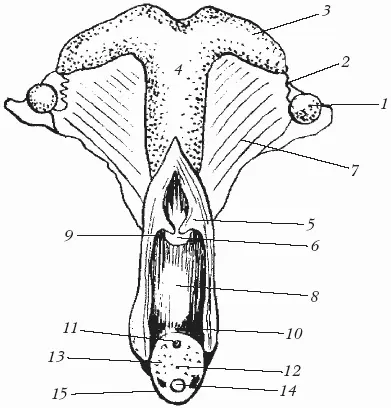

Половые органы самок включают парные органы (яичники, маточные трубы) и непарные (матка, влагалище, преддверие влагалища и наружные половые органы) (рис. 16).

1 – яичник; 2 – яйцепровод; 3 – рог матки; 4 – тело матки; 5 – шейка матки (вскрыто); 6 – наружное отверстие матки; 7 – широкая связка матки; 8 – влагалище (вскрыто); 9 – свод влагалища; 10 – преддверно-влагалищная складка; 11 – наружное отверстие уретры; 12 – преддверие влагалища; 13 – малые преддверные железы; 14 – большие преддверные железы; 15 – клитор